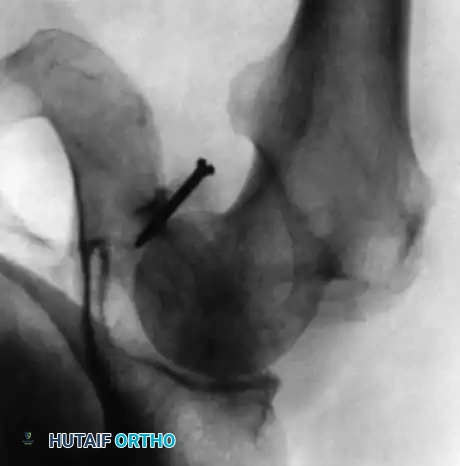

Standard orthogonal radiography is often insufficient for diagnosing the soft-tissue etiology of recurrent hip instability. Large-volume arthrograms are highly instrumental in the preoperative assessment, allowing the surgeon to visualize capsular redundancy, synovial outpouchings, and labral blunting.

Furthermore, the integration of advanced cross-sectional imaging has revolutionized preoperative planning. Klein et al. demonstrated that combining Computed Tomography (CT) with arthrography provides unparalleled spatial resolution to precisely locate capsular tears and labral avulsions prior to surgical intervention.

Fig. 45-18A: Arthrogram in recurrent posttraumatic hip dislocation. On the anteroposterior view, the contrast material fails to remain contained within the anatomical hip joint. Instead, it pools at the neck region, escaping through a massive capsular rent inferiorly.

Fig. 45-18B: When the head and neck of the femur are rotated for a lateral view, the contrast material is clearly visualized flowing into a large, uncontained synovial sac posteriorly, confirming the loss of capsular integrity.